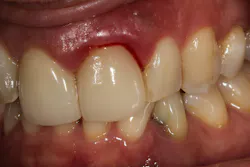

Recently several patients inquired about “why my gums still bleed” after they receive a professional cleaning with their dentists. The second question they ask is, “Is this normal?”

There are a multitude of reasons why patients may not respond properly to periodontal therapy or why their gums still bleed after a dental cleaning (figure 1).1 Of tantamount importance is to discern why previous therapy has not worked prior to reinitiating treatment or simply “giving the patient another cleaning.”